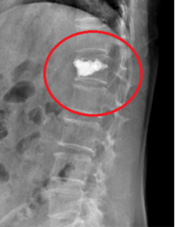

因骨質疏鬆塌陷的椎體,稱為壓迫性骨折

經由經皮椎體成形術填充骨水泥固定骨折

經皮椎體成形術在骨折的椎體內灌注人工骨水泥,快速地提供椎體足夠的穩定性,也能夠防止椎體過度的塌陷,這種手術稱為「經皮椎體成形術(percutaneous vertebroplasty)」,可以在短時間內緩解疼痛,加速病人恢復生活自理。